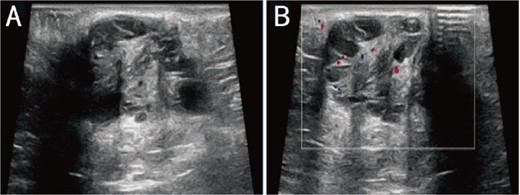

A 38-year-old married female patient presented with a lump near her anus 10 years ago, without apparent cause or symptoms such as redness, swelling, heat, or pain, nor cough, abdominal pain, or diarrhea. No specific treatment was administered. The patient now reports that the lump has grown larger and is accompanied by increasing swelling and discomfort. Seeking further diagnosis and treatment, she visited our outpatient department, where she was admitted with the condition “perianal lump.” Physical examination revealed a body temperature of 36.5°C, pulse rate of 86 beats/min, respiratory rate of 19 beats/min, and a blood pressure of 134/85 mmHg. Admission symptoms include perianal swelling and pain, with itching; no signs of fever, chills, rupture, or pus discharge; bowel movements once or twice daily, and normal urination. The patient has one child and underwent a lateral epidural resection 12 years ago due to natural childbirth. Specialist examination revealed a 4-cm lump with a hard texture at 7–11 o’clock next to the anus, and a radial surgical incision at the 7 o’clock anal margin. Digital rectal examination found no lump, depression, or induration in the anus, and no blood on fingertips. The initial diagnosis was a perianal lump. Auxiliary examinations included ultrasound, which revealed a 4-cm lump in the subcutaneous soft tissue near the anus with minor blood flow signals within and around it, suggestive of an inflammatory lesion (Fig. 1A and B); and pelvic MRI, which suggested a left perianal lump consistent with a perianal abscess (Fig. 2A and B). Under spinal anesthesia, the perianal lump was removed, and postoperative pathology confirmed the presence of endometriosis (Fig. 3).

Ultrasound: (A) 2D ultrasound shows a mixed echo with a range of about 4 cm in the subcutaneous soft tissue around the left side of the anus, presenting as cystic-solid; (B) color doppler shows a small amount of punctate blood flow signal inside and around the mixed echo.